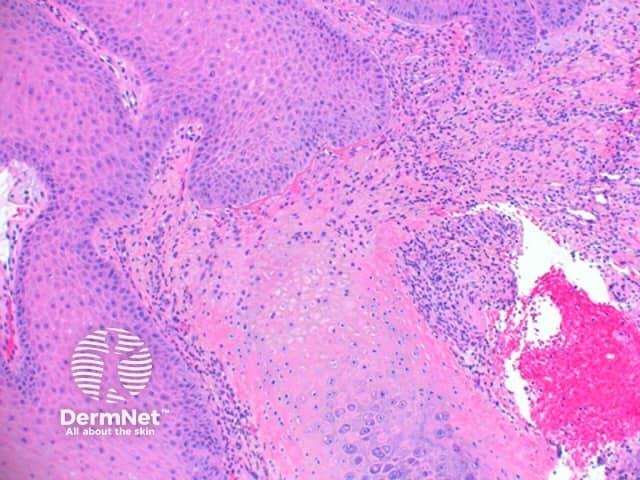

Scanning power view of chondrodermatitis nodularis helicis shows a wedge-shaped dermal alteration extending through to the superficial cartilage (Figure 1). The epidermis may show a focal zone of orthokeratosis and scale crust overlying moderate epidermal hyperplasia (Figure 2). Frequently there will be superficial epidermal ulceration. There is a zone of eosinophilic fibrinoid material overlying the affected area of cartilage, with the blurring of the superficial cartilage and altered staining (Figure 3). There may be adjacent perichondrial thickening.

Figure 2